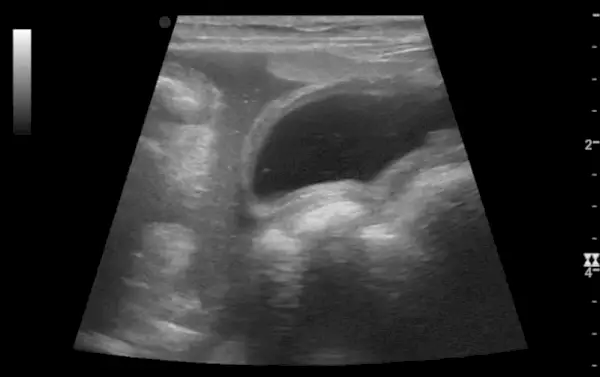

Ha a kutya stabilizálódik, megkezdődik az ok feltárása. A kutyák belső vérzésének diagnosztizálása különféle teszteket igényelhet, beleértve a vérvizsgálatot és a képalkotást. További véralvadási tesztekre vagy szövetmintavételre lehet szükség.